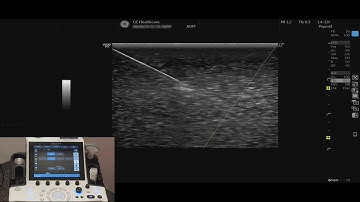

LOGIQ P9 Tutorials: B-Flow